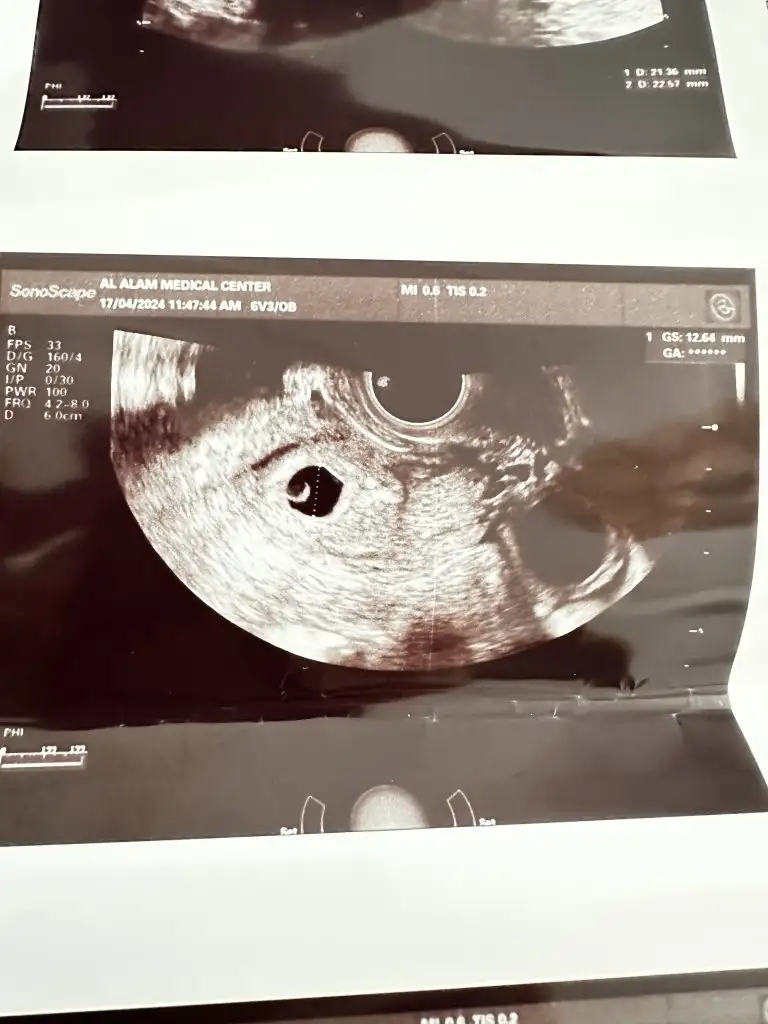

Merhaba hanımlar bende 20 Martta hamile olduğumu öğrendim beta hcg 2226 çıktı aynı gün keseyide gördük.10 gün sonra kalp atışını duyarız dedi. Bugün doktora gittim 6+3 teyiz kesen büyümüş dedi ama kalp atışı duyamadı. Vajinal ultrasonla bakmak istedi onu da ben istemedim o zaman biraz daha bekleyelim dedi ama ben kalp atışı olmadığı için telaşlandım biraz sizce normal mi ?